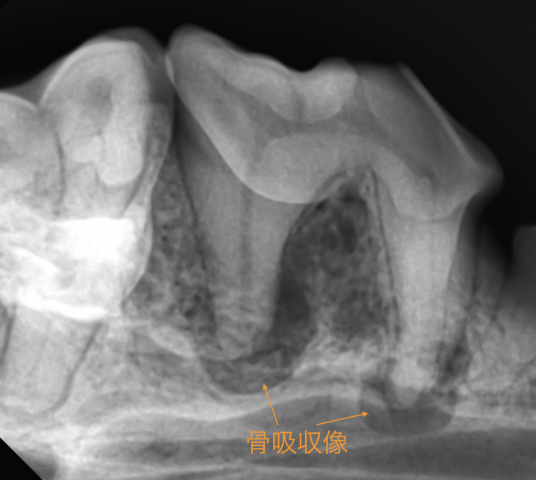

また歯科用レントゲンで、歯の中、歯肉の中の状態を確認する事も重要です。

歯科用レントゲンにて、根尖周囲病巣が確認された場合は抜歯を実施します。